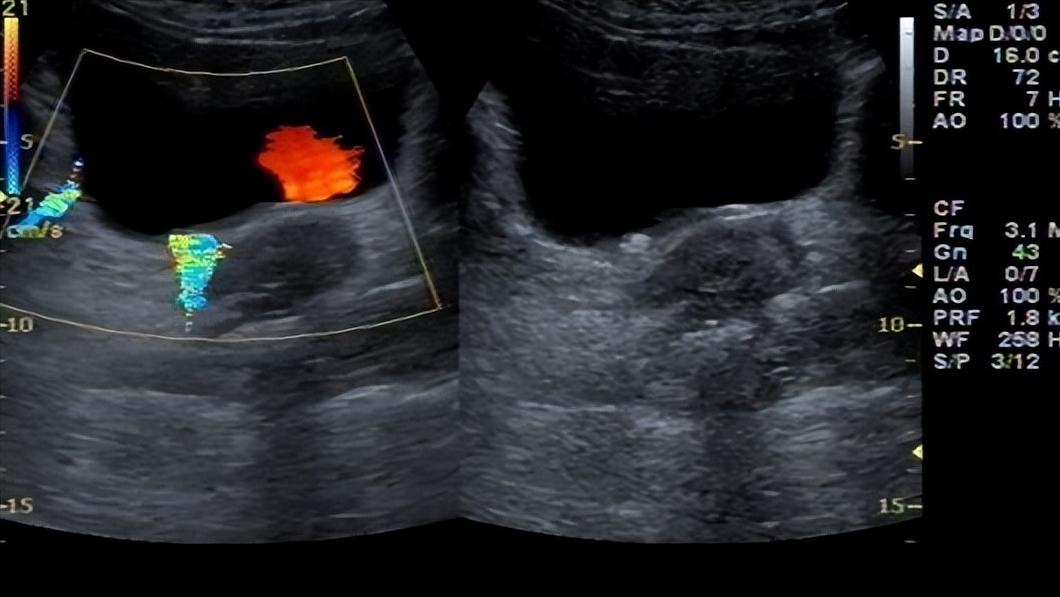

对于泌尿系统结石的诊断,临床上最常用的方式是彩超检查。因为彩超检查不仅准确、无损伤、便捷,还能判断发生部位,具有较高的临床应用价值。

一般情况下,在对患者的输尿管、肾脏、尿道和膀胱进行彩超检查时,不同的部位其声像图表现有所差异。

例如肾结石的声像图表现为强回声光团,且光团后放伴随声影,结石成分的不同致使结石的性状也多种多样。而膀胱结石则表现为弧形强光带,伴有后方声影,如果为数毫米小结石可能无声影,或只有淡声影。